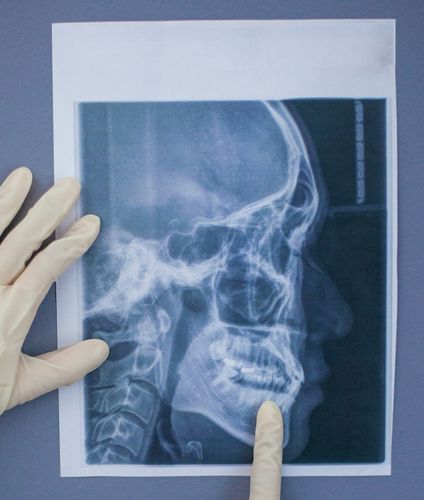

Cephalogram

A Cephalogram, also known as a Cephalometric X-ray

Cephalogram is a specialized diagnostic imaging technique that provides a lateral (side) view of the head, capturing detailed images of the skull, jaw, teeth, and surrounding soft tissues. This imaging modality is predominantly utilized in orthodontics and maxillofacial surgery to assess skeletal relationships and plan appropriate treatments.